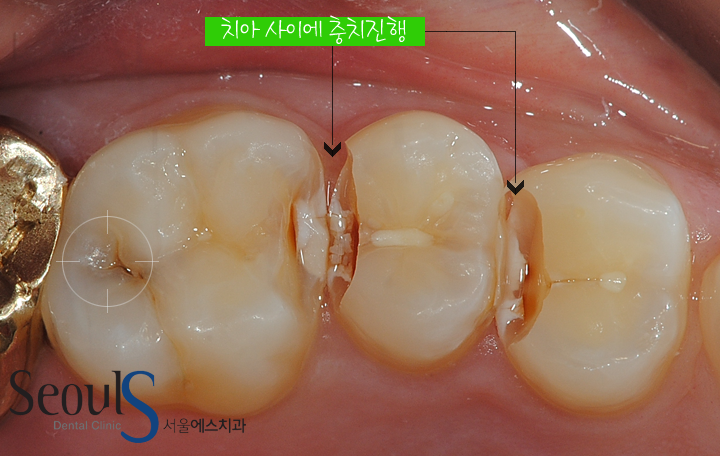

치아 사이에 충치가 진행되고 있는 모습으로

사이에 낀 음식물이 제거 되지 않아 치아 사이를 기준으로 양 옆 치아 속으로 충치가 진행되고 있고

치아 속으로 진행되고 있는 충치가 검게 비춰보입니다

이렇게 치아 사이를 시작으로 치아 속으로 충치가 진행되면 잘 보이지 않아 발견하기 어렵습니다